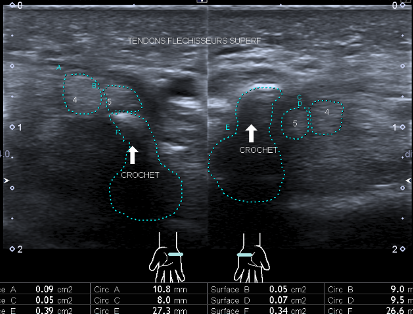

Luxation antérieure douloureuse des fléchisseurs 4 et 5 sur le versant palmaire du

crochet de l’os crochu comme complication d’une incision du LTC (rétinaculum des fléchisseurs)

lors de l’opération du tunnel carpien.

A propos de deux cas:

• Cas 1

Femme de 79 ans avec tuméfaction douloureuse de l’hypothénar 3 ans après cure du

tunnel carpien.

Cas 2

Femme de 54 ans avec douleurs en regard du pisiforme dix semaine après cure du

tunnel carpien. L’examen montre une luxation des fléchisseurs des 4 et 5